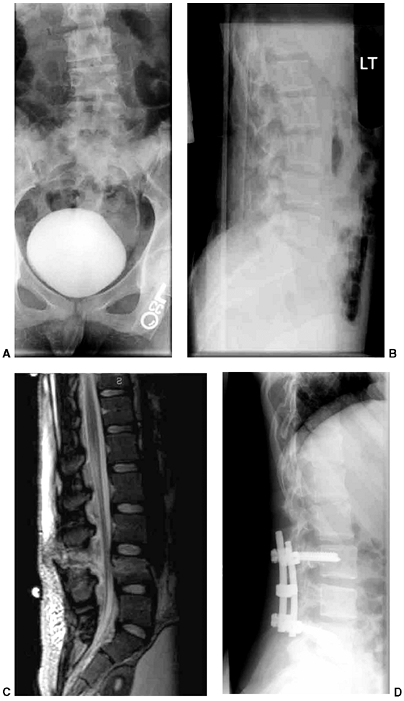

![]() |

|

Figure 33.3 Distal tibial growth arrest. A: Distal tibial physeal Salter-Harris type IV injury treated with cast immobilization without reduction. B:

Two years later, there is varus angulation to the distal tibia from a medial physeal bar. The Harris growth arrest line is not parallel to the distal physis, and does not extend across the entire width of the metaphysis. |